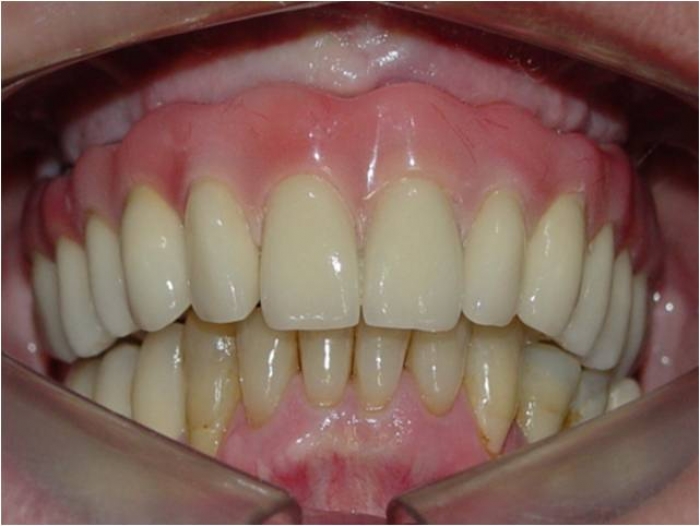

Prótese fixa em porcelana instalada

Sorriso final, do caso terminado em Julho de 2009